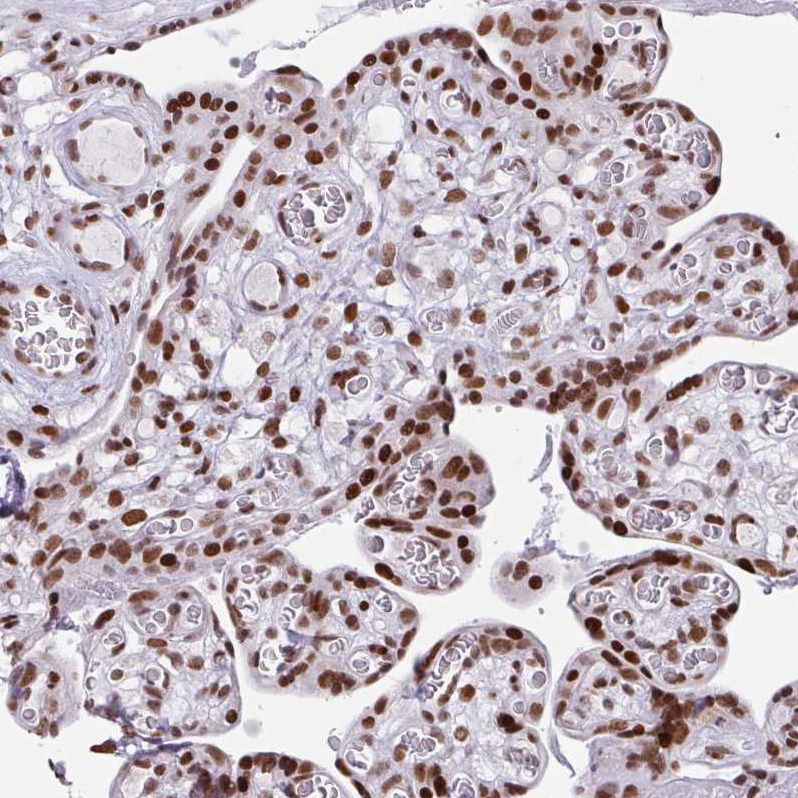

Immunohistochemical staining of human bone marrow shows strong nuclear positivity in hematopoietic cells.